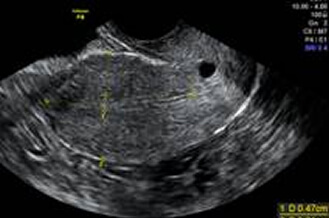

子宮肌瘤

超音波探頭伸入陰道後,可以縮短探頭與子宮和卵巢的距離,看到子宮和卵巢更多的細節。檢查約2~3分鐘內可完成。